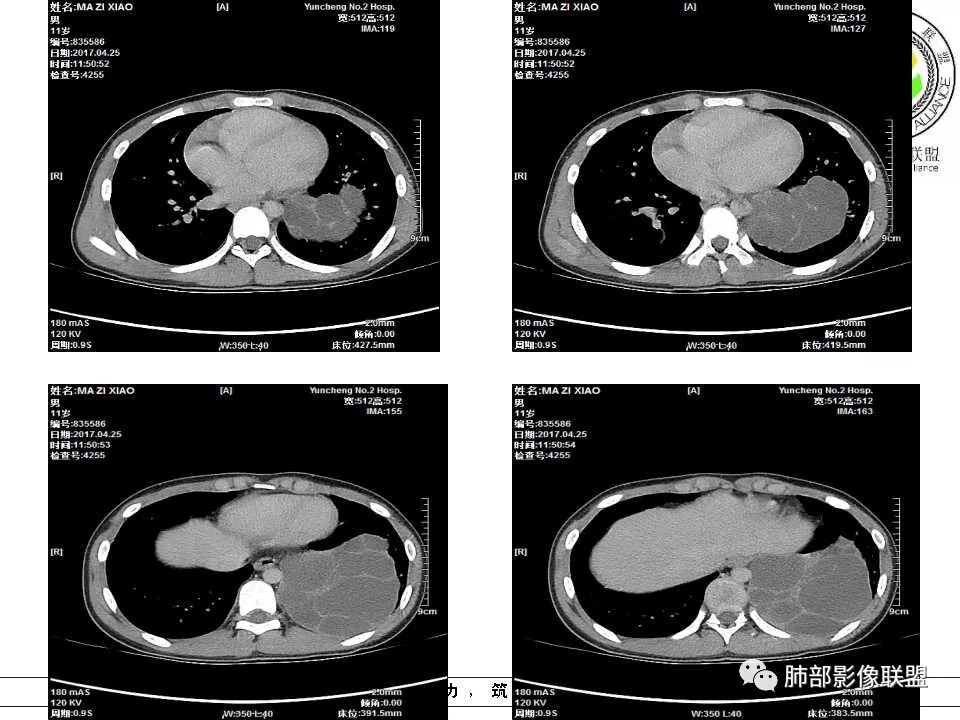

左下肺囊性占位,多发分隔,增强分隔及边缘强化,腹主动脉供血,考虑肺隔离征。

儿童左下肺囊性占位,多发分隔,增强分隔可见强化,腹主动脉供血,肺隔离征。

左肺下叶病灶,囊性为主,内见分隔,边界清晰,首先考虑良性病变,增强可见体循环供血,考虑肺隔离症

儿童,左下病变,边界清,囊性,分隔明显,体循环供血,肺隔离症。

左下肺囊性团块灶,多发分隔,增强分隔及边缘强化,主动脉供血,考虑肺隔离症,叶外型。

左下肺肿块,内部见多分隔,囊性密度,增强见腹主动脉分支、肺动脉供血,考虑肺隔离症,鉴别支气管囊肿

儿童,左下肺多房囊性占位,增强分隔强化,腹主动脉供血,肺隔离征。

11岁男患,左肺下叶见囊性病变,期内见分隔,增强扫描见强化,供血血管清晰,考虑肺隔离症,不除外多房性囊性病变。

男,11岁,左肺下叶囊性包块,形态不规则,内有分隔,包膜及分隔明显强化,主动脉供血,肺静脉引流,基底段支气管显示不清,首先考虑常见病肺隔离症,支气管囊肿不排除

11岁儿童,左下囊性占位,内有分格,强化时可见体循环供血,发生在左下叶内带的囊性或囊实性,肺气肿样改变的首先要考虑肺隔离症,